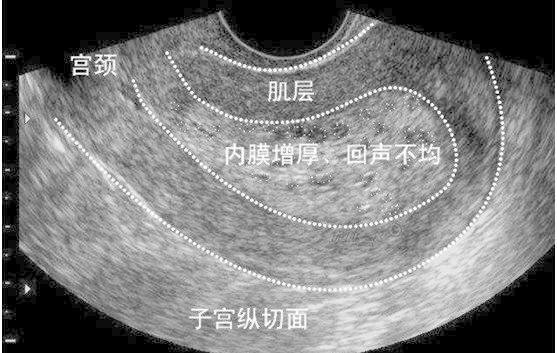

子宫内膜不均是超声回声的一种描述,通常是由于内膜下的血管分布不均所导致的,对于备孕的女士如果超声显示“子宫内膜回声不均”一定要行宫腔镜检查,并治疗病变,以保证良好的宫腔环境,从而提高妊娠率;对于年龄较大的女士则要宫腔镜结合病理,排除恶性病变。

子宫内膜变化是卵巢的内分泌即雌、孕激素作用而出现,与卵泡发育的排卵过程一致。排卵前,卵巢以分泌雌激素为主,使内膜仅发生增殖性变化。在排卵后期在雌孕激素联合作用下使子宫内膜发生特殊的分泌性变化,子宫内膜的声像图也有相应的改变。增殖期内膜多呈线状回声,分泌期和月经期由于内膜水肿,腺体分泌,血管增殖,则表现为典型的“三线”征,即外层为高回声的基底层,内层为低回声的内膜功能层,中央的条状高回声为宫腔粘液,(或两层内膜结合线)。

超声是妇产科的主要辅助检查手段,某些疾病的早期,在超声表现不典型,不可能替代病理,遇到超声提示:内膜回声不均时应该警惕以上情况的出现,可以诊断性刮宫送病理结 合宫腔镜检查还要结合临床及其他检查,进一步明确诊断。同时不要紧张,因为有一部分是正常的,如:药物流产后,子宫内膜没有来得及修复,这种情况是正常的,也可见于使⽤外源性雌激素药物等。